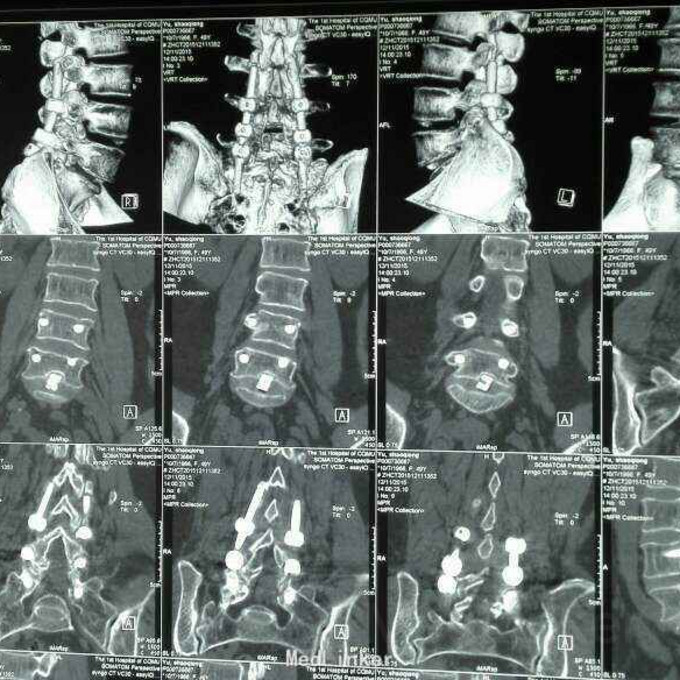

这是今天我在门诊看的一个病人,47岁女性,2年前因腰疼和左下肢疼痛在深圳某医院做了腰椎手术,术后一周又出现左下肢疼痛。半年前来我院就诊,在我科关节组诊断左膝关节结核,行左膝关节融合术。现左膝关节外支架已去除,左下肢无疼痛,有腰痛。该病例诊断治疗有什么不妥的地方?下一步如何处理?